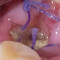

Alo Dokter. Pasien pria berusia 26 tahun datang ke klinik dengan keluhan nyeri di area gigi geraham bawah kanan yang sudah berlangsung selama satu minggu. Pasien menyatakan nyeri terasa berdenyut, terutama saat mengunyah dan saat mengonsumsi makanan panas atau dingin. Pasien membawa hasil rontgen dibawah. Apakah perlu dilakukan tindakan atau cukup dengan obat-obatan saja? Mohon advice, dok, terutama TS dokter gigi 🙏🏼